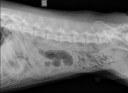

RadioQuiz 14 – Mon chien traîne de la patte

RadioQuiz 13 – Donnez-lui un petit sac

RadioQuiz 12 – Mon chat ne file pas

RadioQuiz 11 – Bulldog traînant d’la patte

RadioQuiz 9 – Carlin portant est de partir du bon pied !

RadioQuiz 8

RadioQuiz 7

RadioQuiz 6 – Ma p’tite chienne a mal à la patte

RadioQuiz 5

RadioQuiz 4